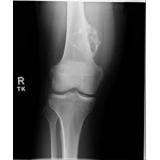

විශේෂයෙන් රුධිර පරික්ෂණ හා එක්ස් රේ පරික්ෂණ

ඇතිවීම වලක්වා ගැනීමට විශේෂිත ක‍්‍රමයක් නැතිමුත් මූලික රෝග ලක්ෂණ එනම් අස්ථි වල එක් ස්ථානයක ඇතිවන කැක්කුම ( විශේෂයෙන් රාත‍්‍රී කාලයේදී පවා) අස්ථි ආශ‍්‍රිතව ගෙඩියක් ඇතිවීම යන අවස්ථා වලදී නොපමාව වෛද්‍ය උපදෙස් ගැනීම මඟින් තත්වය උග‍්‍ර තත්වයට පත්වීම වලක්වා ගත හැක.